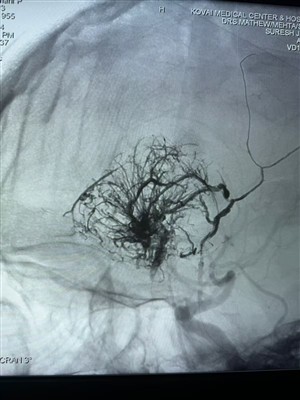

Prvý prípad hypervaskulárneho nádoru hlásený v IndiiS radosťou zdieľam tento prvý prípad hypervaskulárneho nádoru vykonaný v Indii. Bol ošetrený pomocou Lava Liquid Embolic System od NeuroSafe Medical Co., Ltd.. Vďaka Dr. Mathew Cherian. Bol priekop...